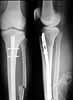

Attached is an example of the "expert" level - the last case. Open lower third tibial shaft fracture, 2 weeks after injury, 30 years old male. The new fracture was revealed when the patient already has been transported from the OR. Tomorrow he is scheduled for its fixation.

It is the first such complication from about 80 tibial nailigs. What is the reason of the fracture, and what is the optimal way to fix it? I plan to apply external fixator, and 45 degree screw, and maybe 1-2 interfragmentary screw.

THX in advance.

![]() |

I don't think I've seen such a proximal tibial fracture ? through nail entry site in many more than 80 IM nailings. How did you prepare the entry and introduce the nail? Any information that might help us avoid similar problems? Presumably no evidence of fracture there before?

I'm not sure the 45 degree screw (I assume through the nail) would do much good - too low.

I'd fix with 2 lag screws from front to back, angled proximally, one on each side of the nail, starting low enough to have thick enough bone anteriorly. I'd probably use a posteromedial plate to "neutralize", but imagine the same could be done with an ex fix.

allow to mobilize the knee as well as partial WB. DTIG> Do let us know what you have done.Best of luck. I applied a simple Ilizarov frame, and after reduction inserted a locking

screw into a 45 degree hole and two AP screws "miss a nail". X-rays

attached. Best regards, Date: Wed, 18 Jun 2003 09:36:40 -0400 From: James Carr Nice bailout Alex. One cause of proximal fracture in addition to starting